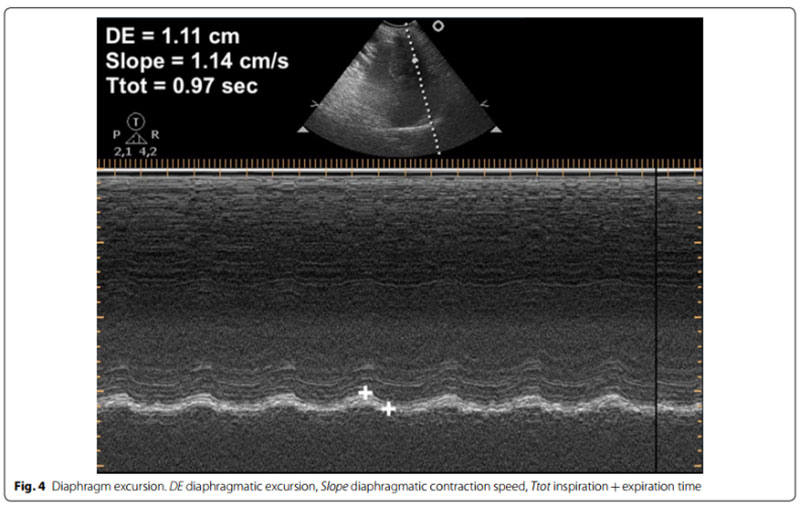

膈肌超声

2个膈肌超声指标可指导脱机

a.膈肌活动度(DE, cm):呼吸时膈肌最大活动范围

b.膈肌增厚分数 (DTF, %):DTF=(平静吸气末膈肌厚度-平静呼气末膈肌厚度)/平静呼气末膈肌厚度×100%